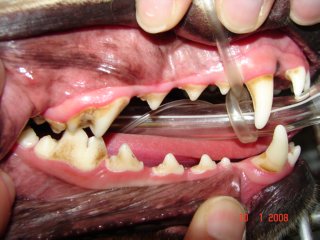

In stage 2 (early periodontitis), the inflammation of the gums are worse. The teeth are covered with significant amount of tartar. The pet’s mouth is painful.

In stage III (established periodontitis) the gum lining starts receding. The bone loss is getting worse and roots are being exposed.